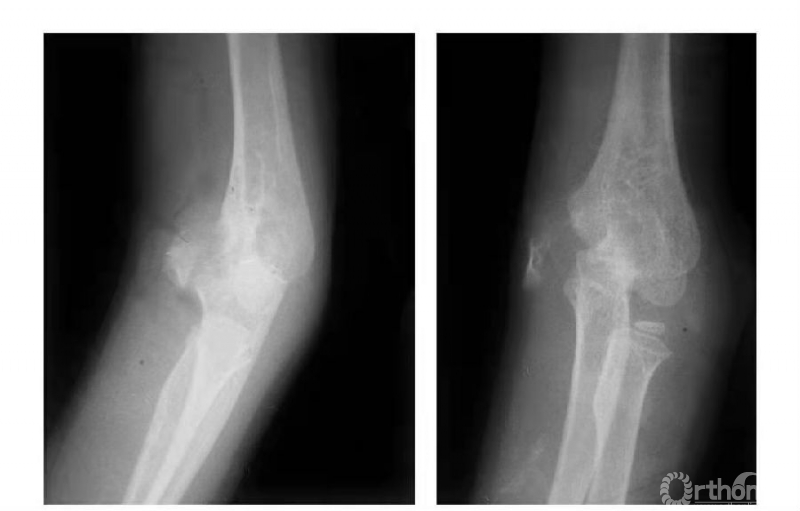

例3:肱骨内髁骨折,骨块向前上移位,并上尺桡关节分离致尺肱关节不稳,且桡骨干近段呈代偿性粗大(图6)。

图6

例4:肱骨内髁滑车骨折,且骨块内移,致骨骺因损伤而早闭,并形成肘内翻畸形(图7)。

图7